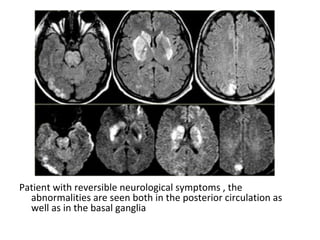

Patient with reversible neurological symptoms , the

abnormalities are seen both in the posterior circulation as

well as in the basal ganglia

Four days later most of the abnormalities have disappeared